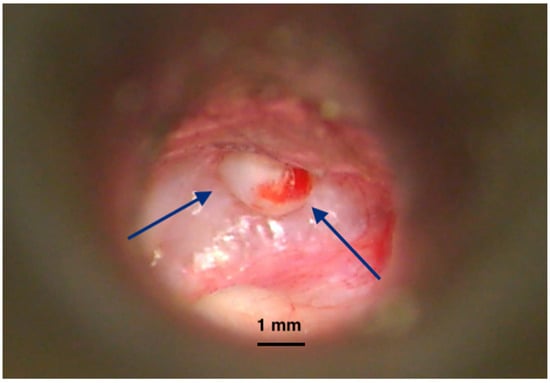

• Congenital and rare, with an intact tympanic membrane (Figure 1);

Figure 1. Intraoperative imaging of a congenital cholesteatoma of the right ear. Tympanic membrane and anterior part of the external canal wall skin have been basculated posteriorly to expose the lesion. No perforation of the eardrum was present before surgery. Congenital cholesteatoma (TM—Tympanic membrane). Picture taken with Zeiss TIVATO 700 microscope (ZEISS Microscopy, Jena, Germany). (from D.C.G’s. personal collection).